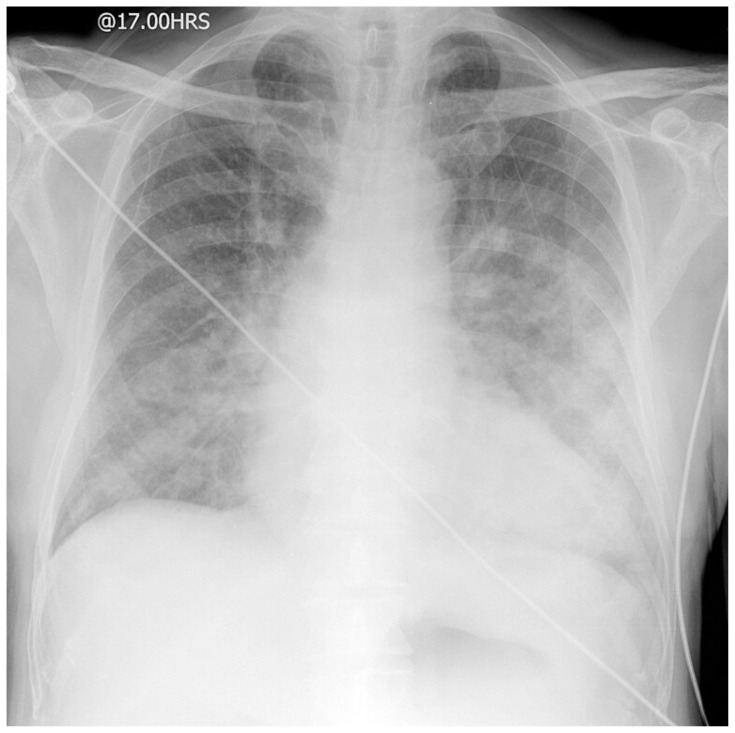

Abstract Image